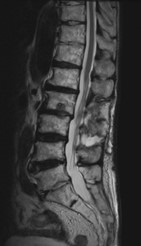

腰で多い病気

• 変形性腰椎症

• 腰椎圧迫骨折

• 腰椎椎間板ヘルニア

• 腰部脊柱管狭窄症

腰痛、お尻からふくらはぎに至る痛み(坐骨神経痛)やしびれ感、間欠跛行(歩くと足に痛みやだるさが生じ、長い距離を歩けなくなる。腰を曲げて休むとおさまる)、膀胱直腸障害(尿の回数が多い)等の症状を伴います。その他、背骨の腫瘍や炎症等も扱います。

治療について

受診された際には問診、診察を行い、画像検査(レントゲン、MRI、CT)や採血検査を行い、診断を付け、治療方針を説明します。 上記のような保存治療を行っても取れない痛みや、手の使いにくさや歩行困難、排尿排便障害などが出現し症状が進行性の場合は手術加療が必要となります。

• 腰椎椎弓切除術

適応となる疾患

腰部脊柱管狭窄症

骨を削って靭帯を切除する除圧術のみで加療可能な患者さんに受けていただく手術です。

• 腰椎後方固定術

腰椎椎間板ヘルニア、変形性腰椎症、腰椎(分離)すべり症など

骨を削って靭帯を切除する除圧術のみで神経症状の改善が困難と判断された場合は、固定術も行います。

• ヘルニア摘出術

腰椎椎間板ヘルニア

痛みやしびれ、足の筋力低下などが薬物療法やリハビリテーションなど保存的治療でも改善しない場合、ヘルニア摘出術を行います。